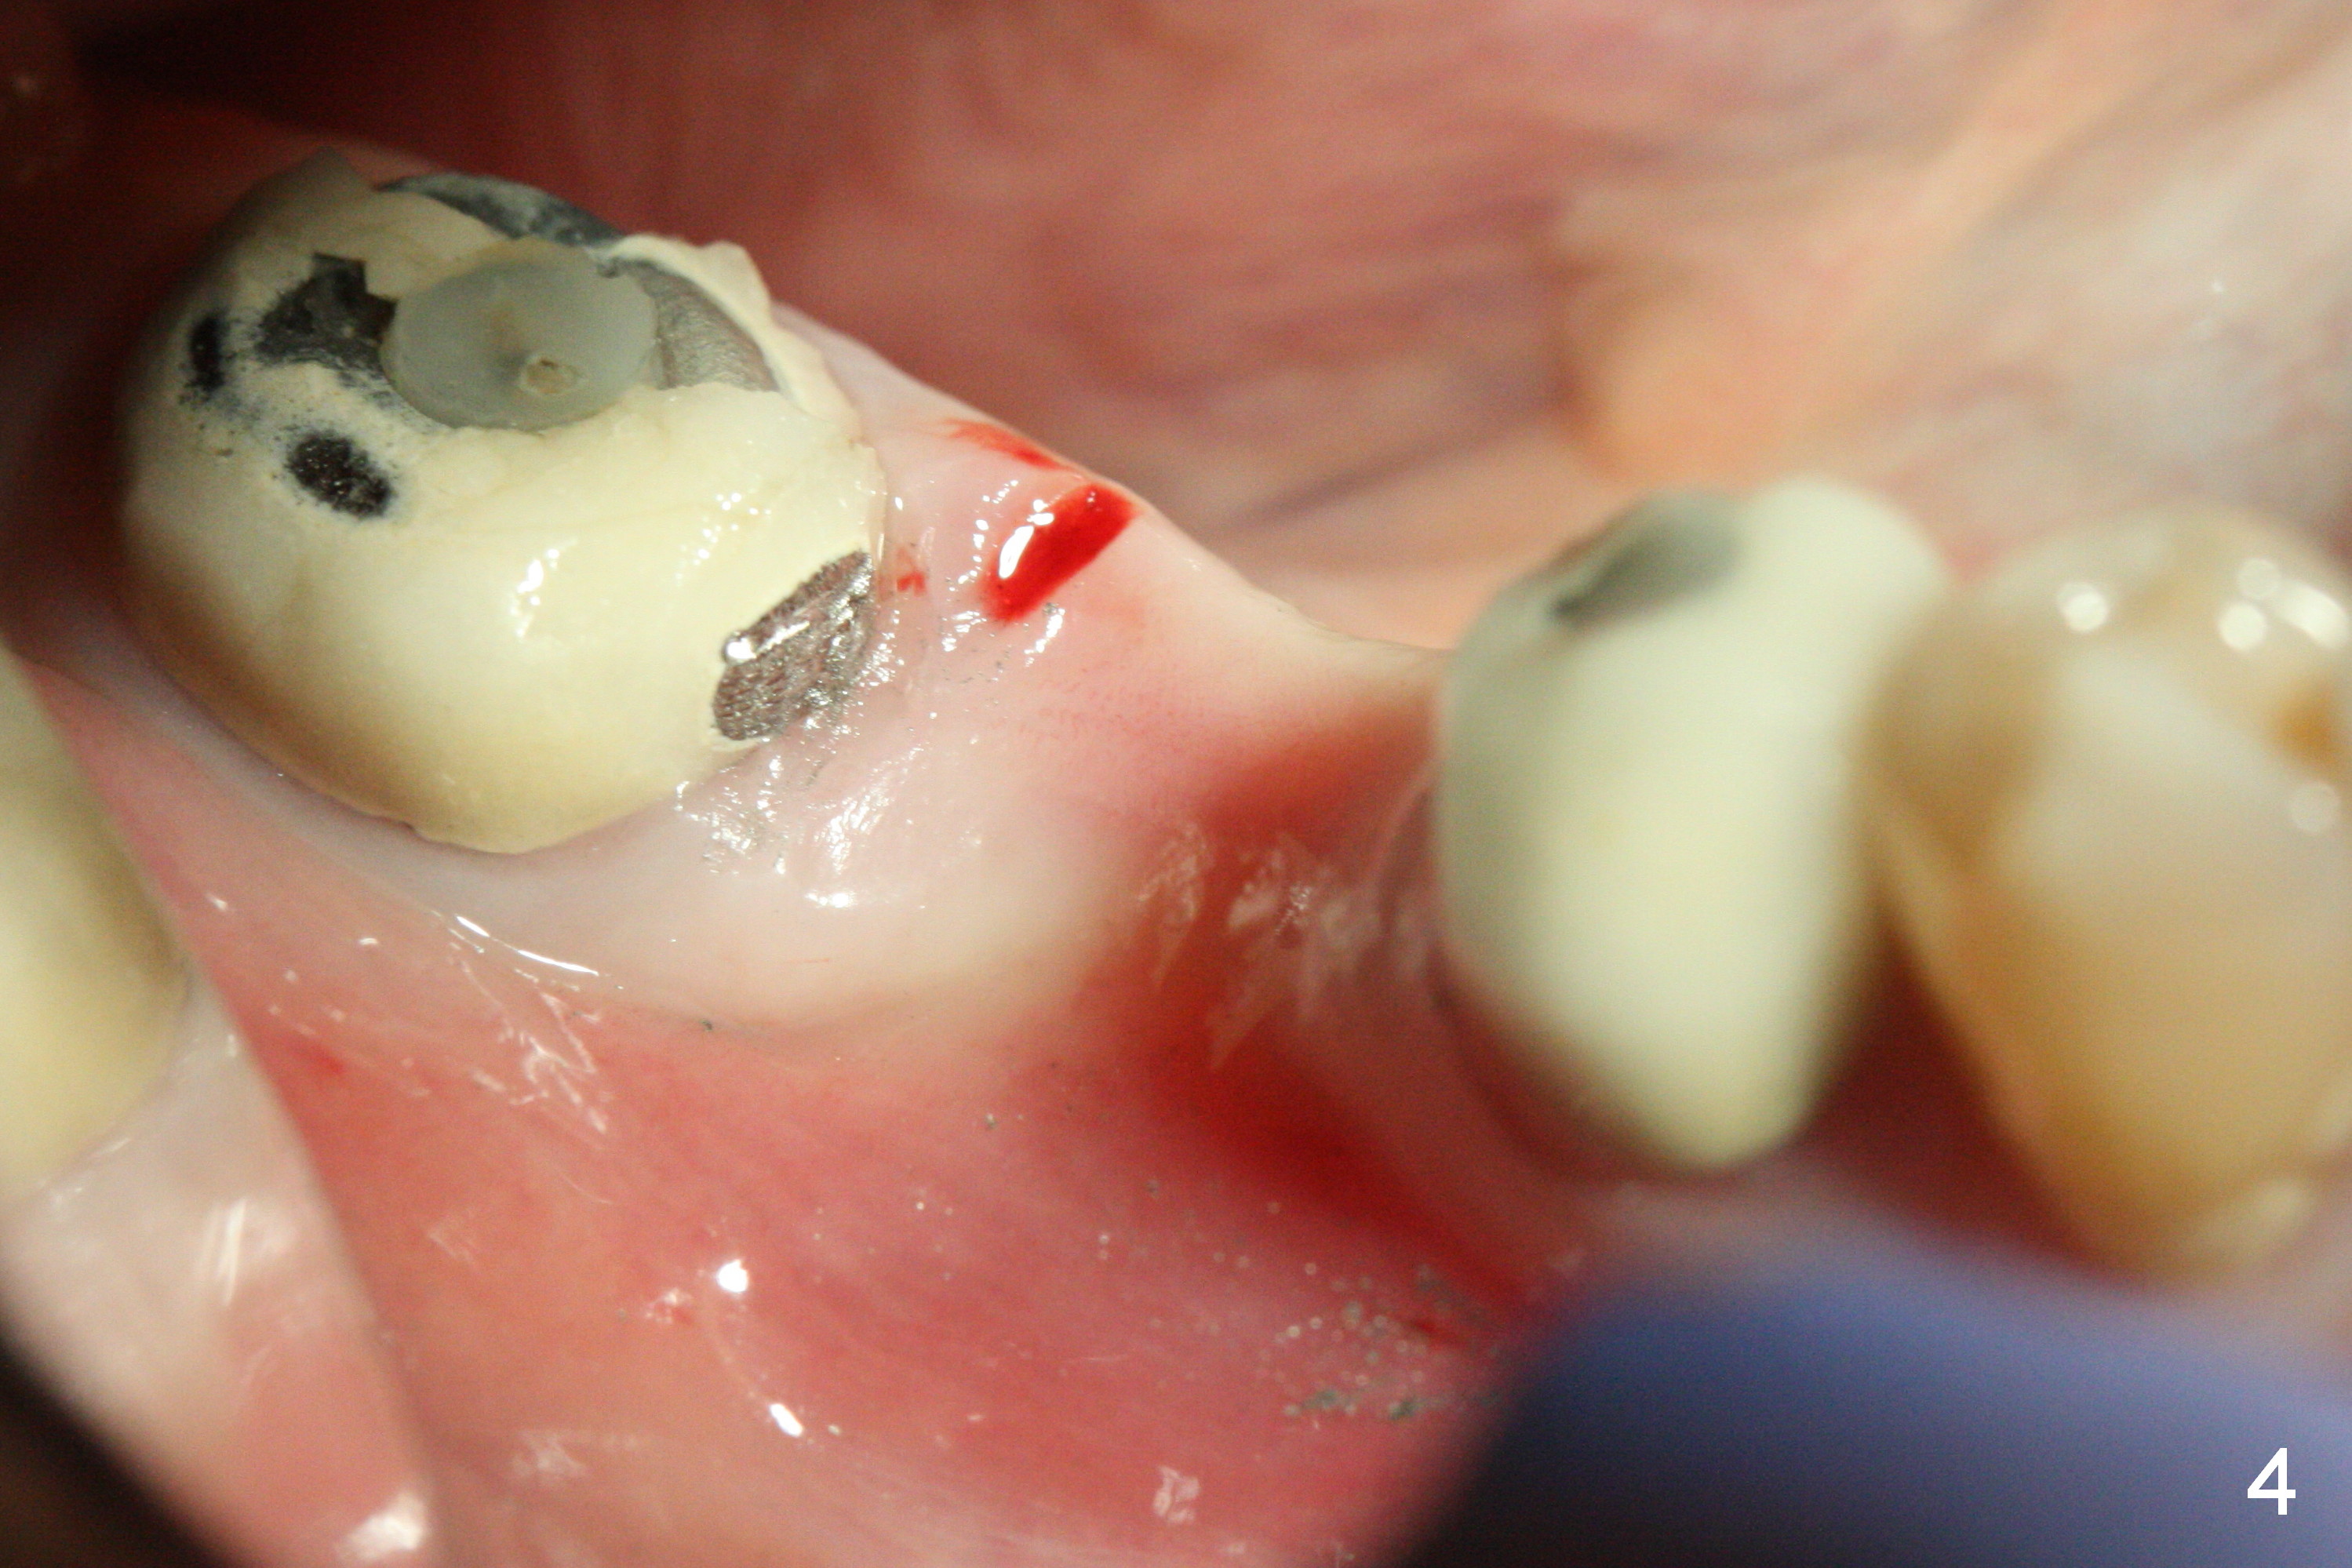

CBCT was taken (Fig.1,2 (P: pontic; S; submandibular fossa)) several months prior to #29 and 31 RCT and #31 porcelain chip (Fig.3). When the bridge is sectioned, the pointed ridge at #30 (Fig.1) is confirmed (Fig.4,5). After flattening the ridge until 6 mm buccolingually (Fig.6 arrowheads), osteotomy is initiated with 1.6 mm drill at 9 mm; there is 2.5 mm clearance from the superior border of the Inferior Alveolar Canal (red dashed line). A 4.5x9(1) mm Magicore is placed with 35 Ncm (insertion torque) after 4.3 mm Magic Drill; a 4.5 mm healing abutment (Fig.7 H). An error occurs because of using 1 mm cuff of the Magicore. Ideally 3 or 4 mm cuff should have been used because of reduction of the ridge by ~ 3 mm (Fig.2). The result of the error is failure of placing the implant at the desirable depth (<9 mm). The coronal threads are exposed and have to be covered by bone graft (autogenous bone and allograft (.5-1.5 mm) (Fig.8 *), followed by collagen dressing. Extra suturing is done to securely close the wound (Fig.9), followed by periodontal dressing (data not shown).